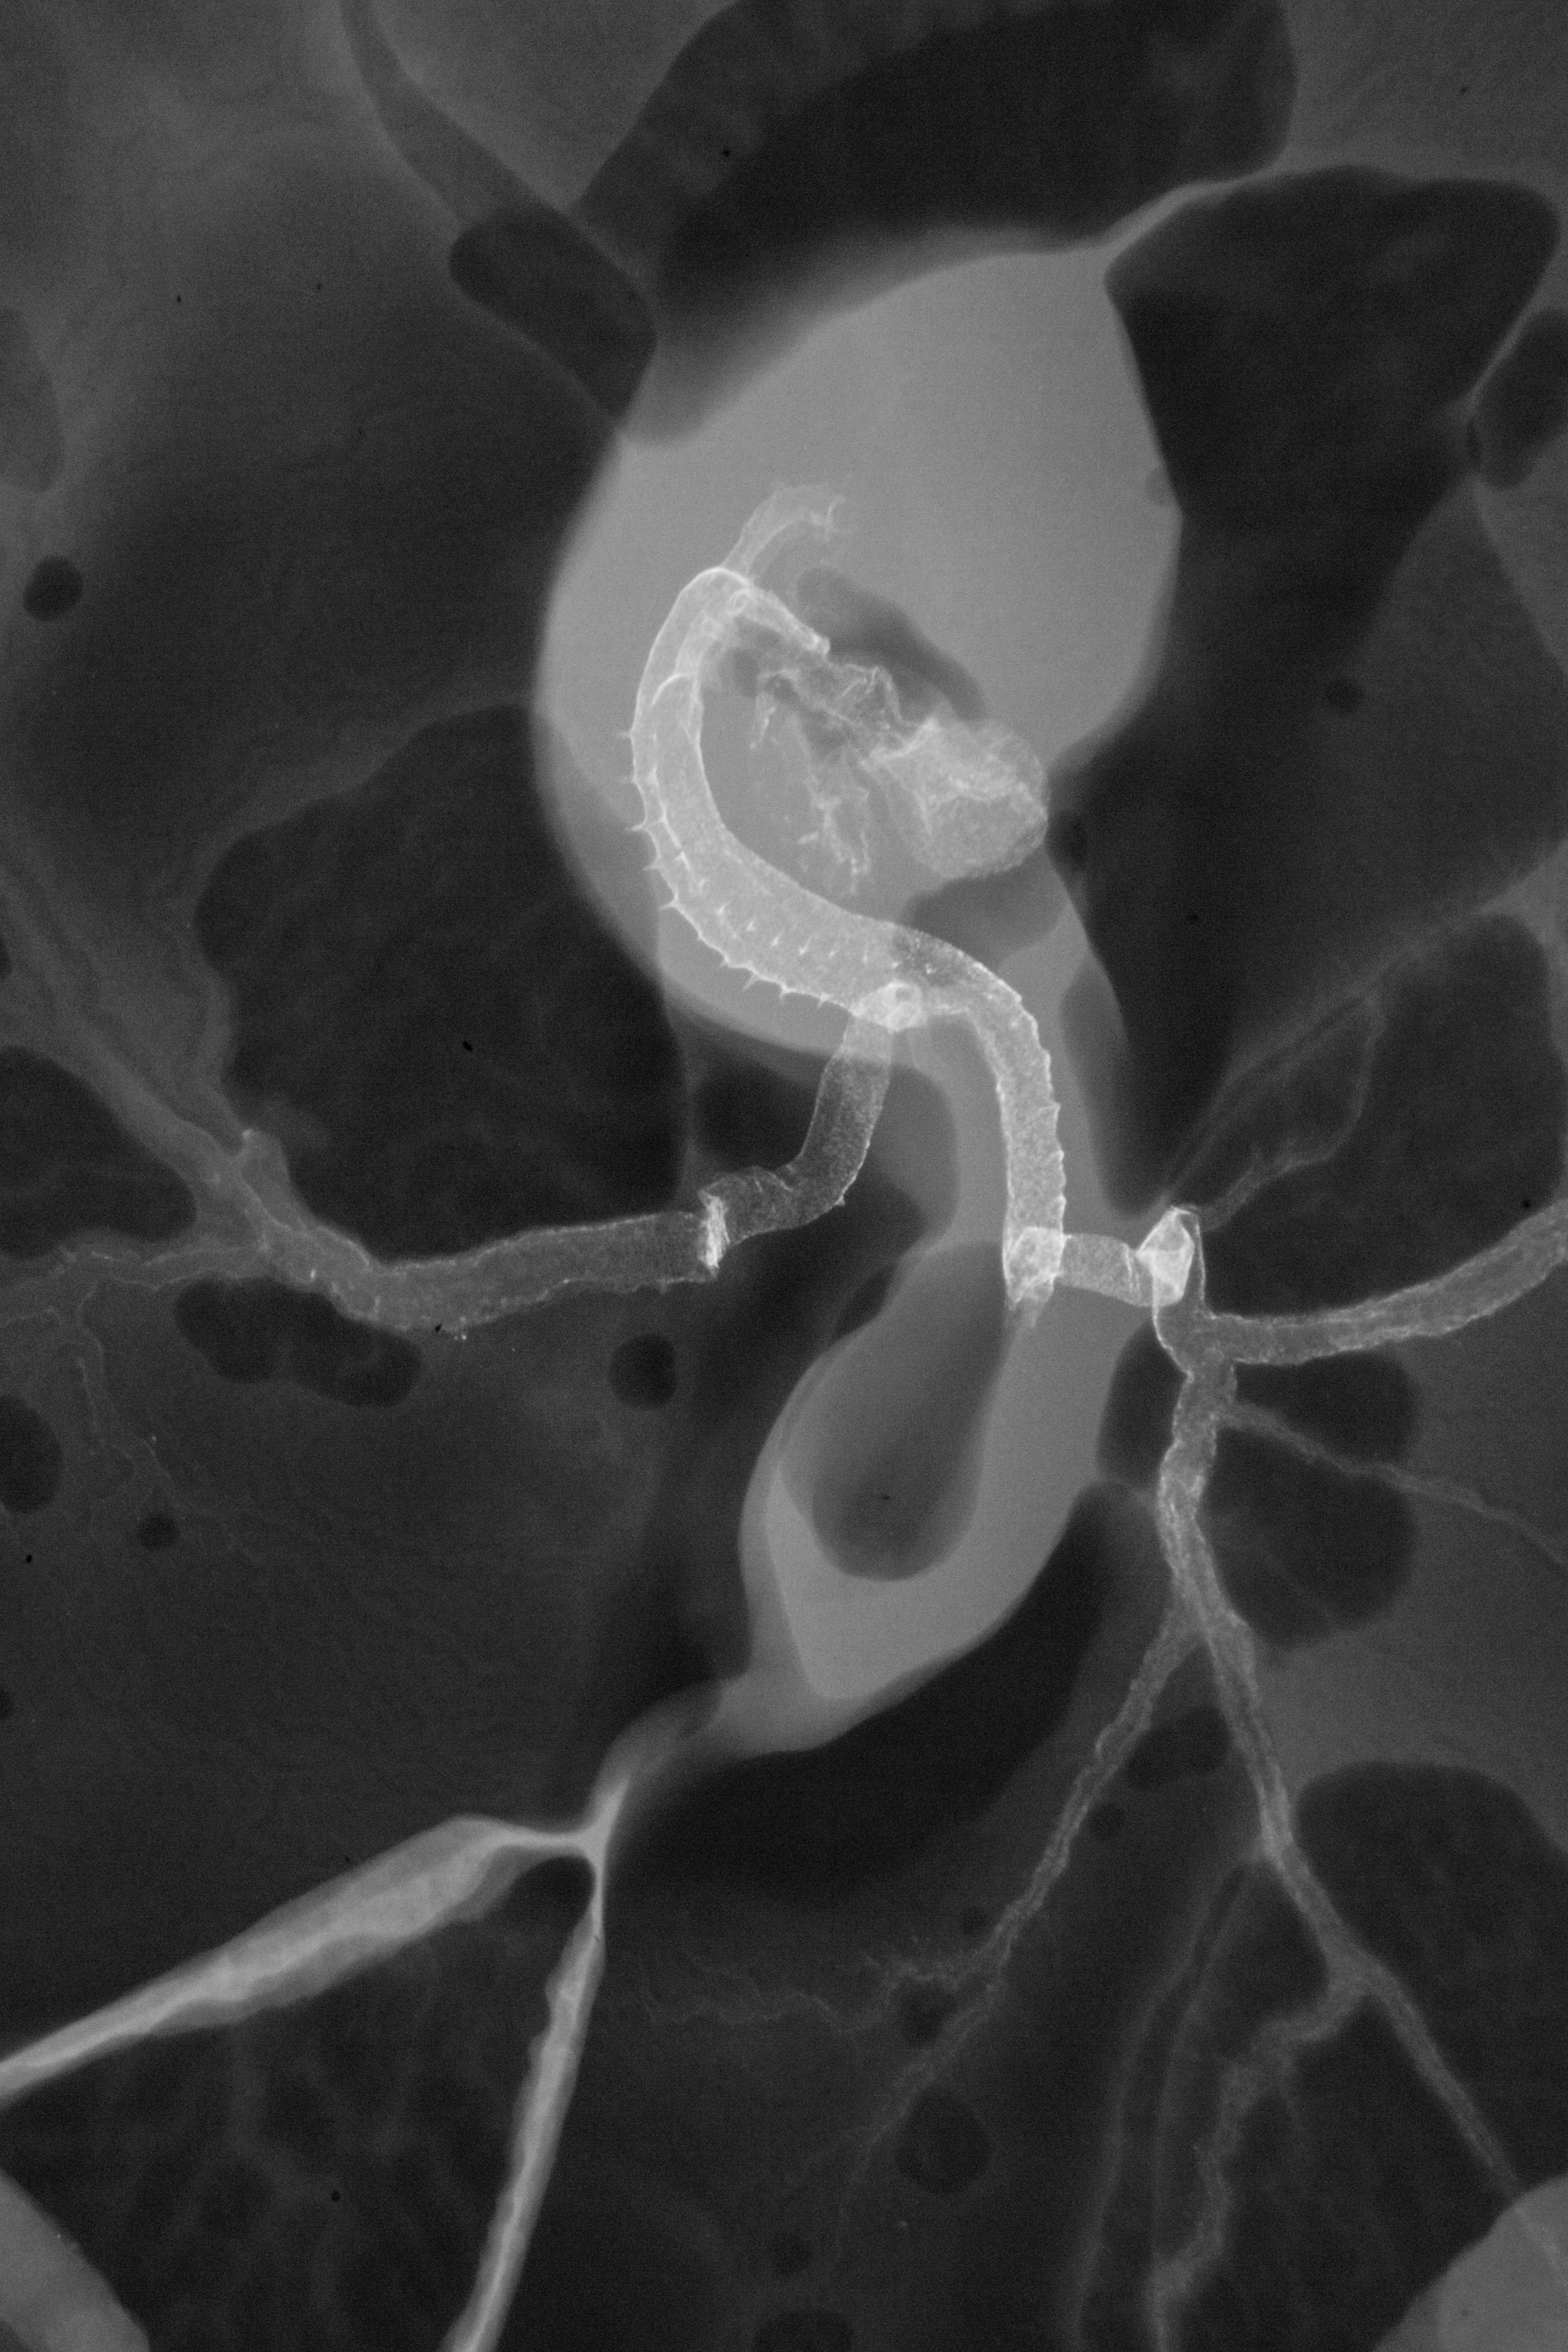

Chick Embryo Microangiography

Hamburger-Hamilton (HH) Stage 16 (approx. 2.1 - 2.5 days)

X-Ray Micrographs